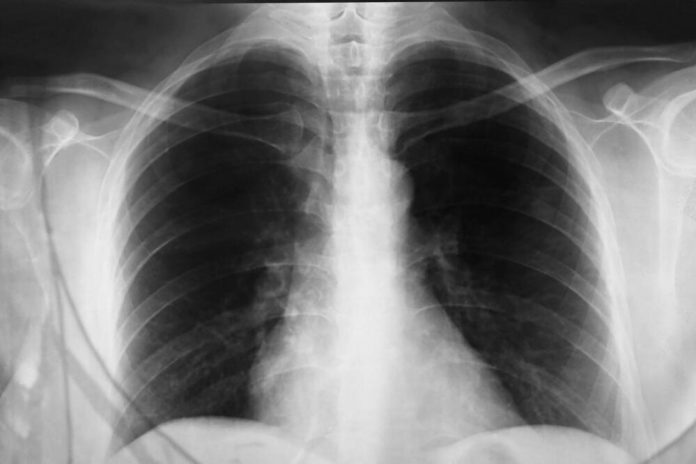

Lečenje upale pluća zavisi od uzročnika bolesti. Dijagnoza se postavlja na osnovu kliničke slike, pregleda pluća i rendgen snimka, a ponekad su potrebne i laboratorijske analize kako bi se tačno odredilo koji uzročnik izaziva bolest. Bakterijska pneumonija zahteva antibiotike, dok se kod virusne infekcije obično lečenje svodi na odmor, unos tečnosti i lekove za snižavanje temperature. U težim slučajevima, hospitalizacija i terapija kiseonikom mogu biti neophodni.